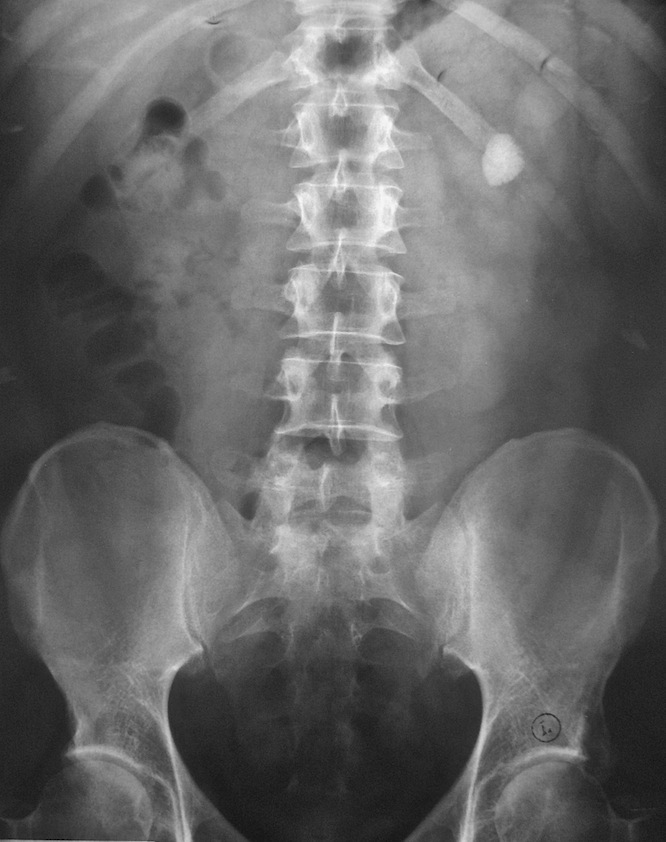

Внутривенная урография – это рентгенологическая диагностика мочевыделительной системы, которая включает почки, уретру и мочевой пузырь. При обычном рентгене мочевыводящие пути исследовать затруднительно. Внутривенная урография позволяет реально оценить состояние почек и мочеточников, а также диагностировать различные патологии мочевыделительной системы. В вену вводится специальное контрастное вещество, которое при попадании в кровоток скапливается в почках, а затем выводится естественным путем.

Готовый рентгеновский снимок принято именовать урограммой или пиелограммой.

Перед проведением исследования пациенту необходимо лечь на рентгеновский стол, сняв предварительно одежду. Врач вводит контрастное вещество в вену, после чего можно ощутить легкое жжение. Препарат попадает в почки и мочеточник, после чего выполняется ряд снимков с интервалом в 5-10 минут. Перед выполнением последнего рентгеновского снимка пациенту может понадобиться опорожнить мочевой пузырь. Процедура внутривенной урографии занимает в среднем от 30 до 60 минут времени. В некоторых случаях исследование может занимать до нескольких часов. После проведения исследования пациент может сразу покинуть кабинет и уйти. Нет никаких ограничений для приема пищи сразу после процедуры.